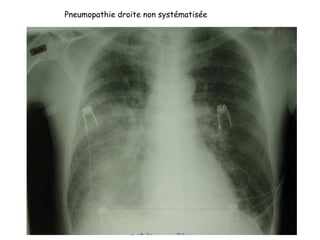

Pneumopathie droite non systématisée